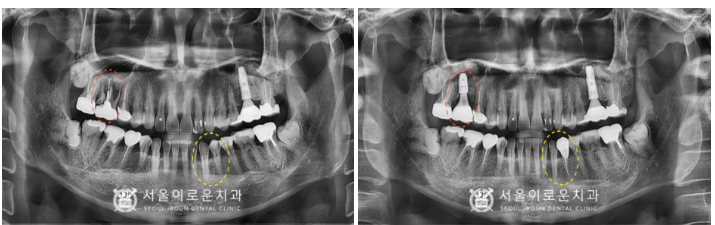

염증조직이 남아 있게 되면

잇몸뼈가 재.생되는데

방해가 될 수 있기 때문에

발치 후 염증을 말끔히 제거한 뒤

상악동 거상술 측방 접근법으로

충분한 뼈이식 후

임플란트 식립을 진행하였는데요.

이식한 뼛가루가

빠져나오지 않고 잘 아물 수 있도록

‘차폐막’으로 덮어 마무리해 드렸습니다.

술 후 파노라마와 3D-CT를 통해

상악동 거상술을 동반한 임플란트가

안정적으로 식립된 것을

체크하였답니다.